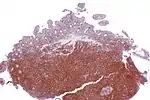

| Micrograph showing mantle cell lymphoma (bottom of image) in a biopsy of the terminal ileum. H&E stain. | |

The history and physical examination may reveal some of the signs and symptoms consistent with Mantle Cell Lymphoma. Biopsy of the involved tissues (such as the lymph nodes, bone marrow, gastrointestinal tract, spleen or other areas) shows the characteristic histopathologic changes of MCL. There are distinct growth patterns of MCL seen on biopsy; these include the diffuse type, nodular type, mantle zone lymphoma and in situ mantle cell lymphoma.[7] In the diffuse growth pattern, there is a diffuse growth of lymphoma cells throughout the lymph node resulting in effacement of the architecture of the lymph node.[7] In the nodular type, there are large nodules of MCL cells in the lymph node with no germinal centers observed.[7] In MCL with expansion of the mantle zone, the lymphoma cells cause expansion of the mantle zone around normal germinal centers.[7] And in MCL in situ, the lymphoma cells are contained within the mantle zone without expansion.[7] Histologically, the lymphoma cells in classic MCL are characterized as small to medium lymphocytes with scant cytoplasm and clumped chromatin with prominent nuclear clefts and the nucleoli are not visible.[7] There are cytologic subtypes; the blastoid subtype, is characterized by round nuclei, fine chromatin with some distinct nucleoli.[7] The pleomorphic subtype is characterized by nuclei that vary in size and shape with some having a cleaved form.[7] The blastoid and pleomorphic subtypes of MCL are associated with a more aggressive course.[7]